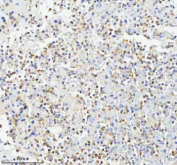

Immunohistochemical staining of GLIPR2 using anti-GLIPR2 antibody. GLIPR2 was detected in a paraffin-embedded section of human lung cancer tissue. Heat mediated antigen retrieval was performed in EDTA buffer (pH 8.0, epitope retrieval solution). The tissue section was blocked with 10% goat serum. The tissue section was then incubated with 2 ug/ml rabbit anti-GLIPR2 antibody overnight at 4oC. Peroxidase Conjugated Goat Anti-rabbit IgG was used as secondary antibody and incubated for 30 minutes at 37oC. The tissue section was developed using an HRP secondary and DAB substrate.